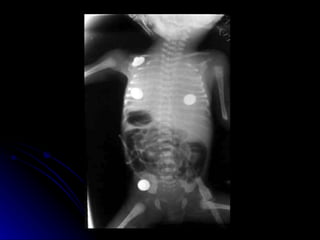

Pulmonary interstitial emphysemaMainly occurs in preterm babies ventilated for HMD Gas trapping in perivascular sheaths Increased incidence at lower gestations

• 31.

• 32.

PIE - Clinicalfeatures Severe hypoxaemia and CO2 retention Deteriorating clinical condition X- Ray Overinflation with gross cystic changes